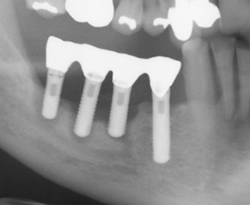

先日来院した患者さんはインプラントのまわりに角化歯肉がない状態のためプラークコントロールができずインプラント周囲炎をおこしていました。歯肉が痩せて薄くなってますす。

先日インプラント治療が終わった患者さんはインプラント手術時、遊離歯肉移植術(FGG)を併用しました。